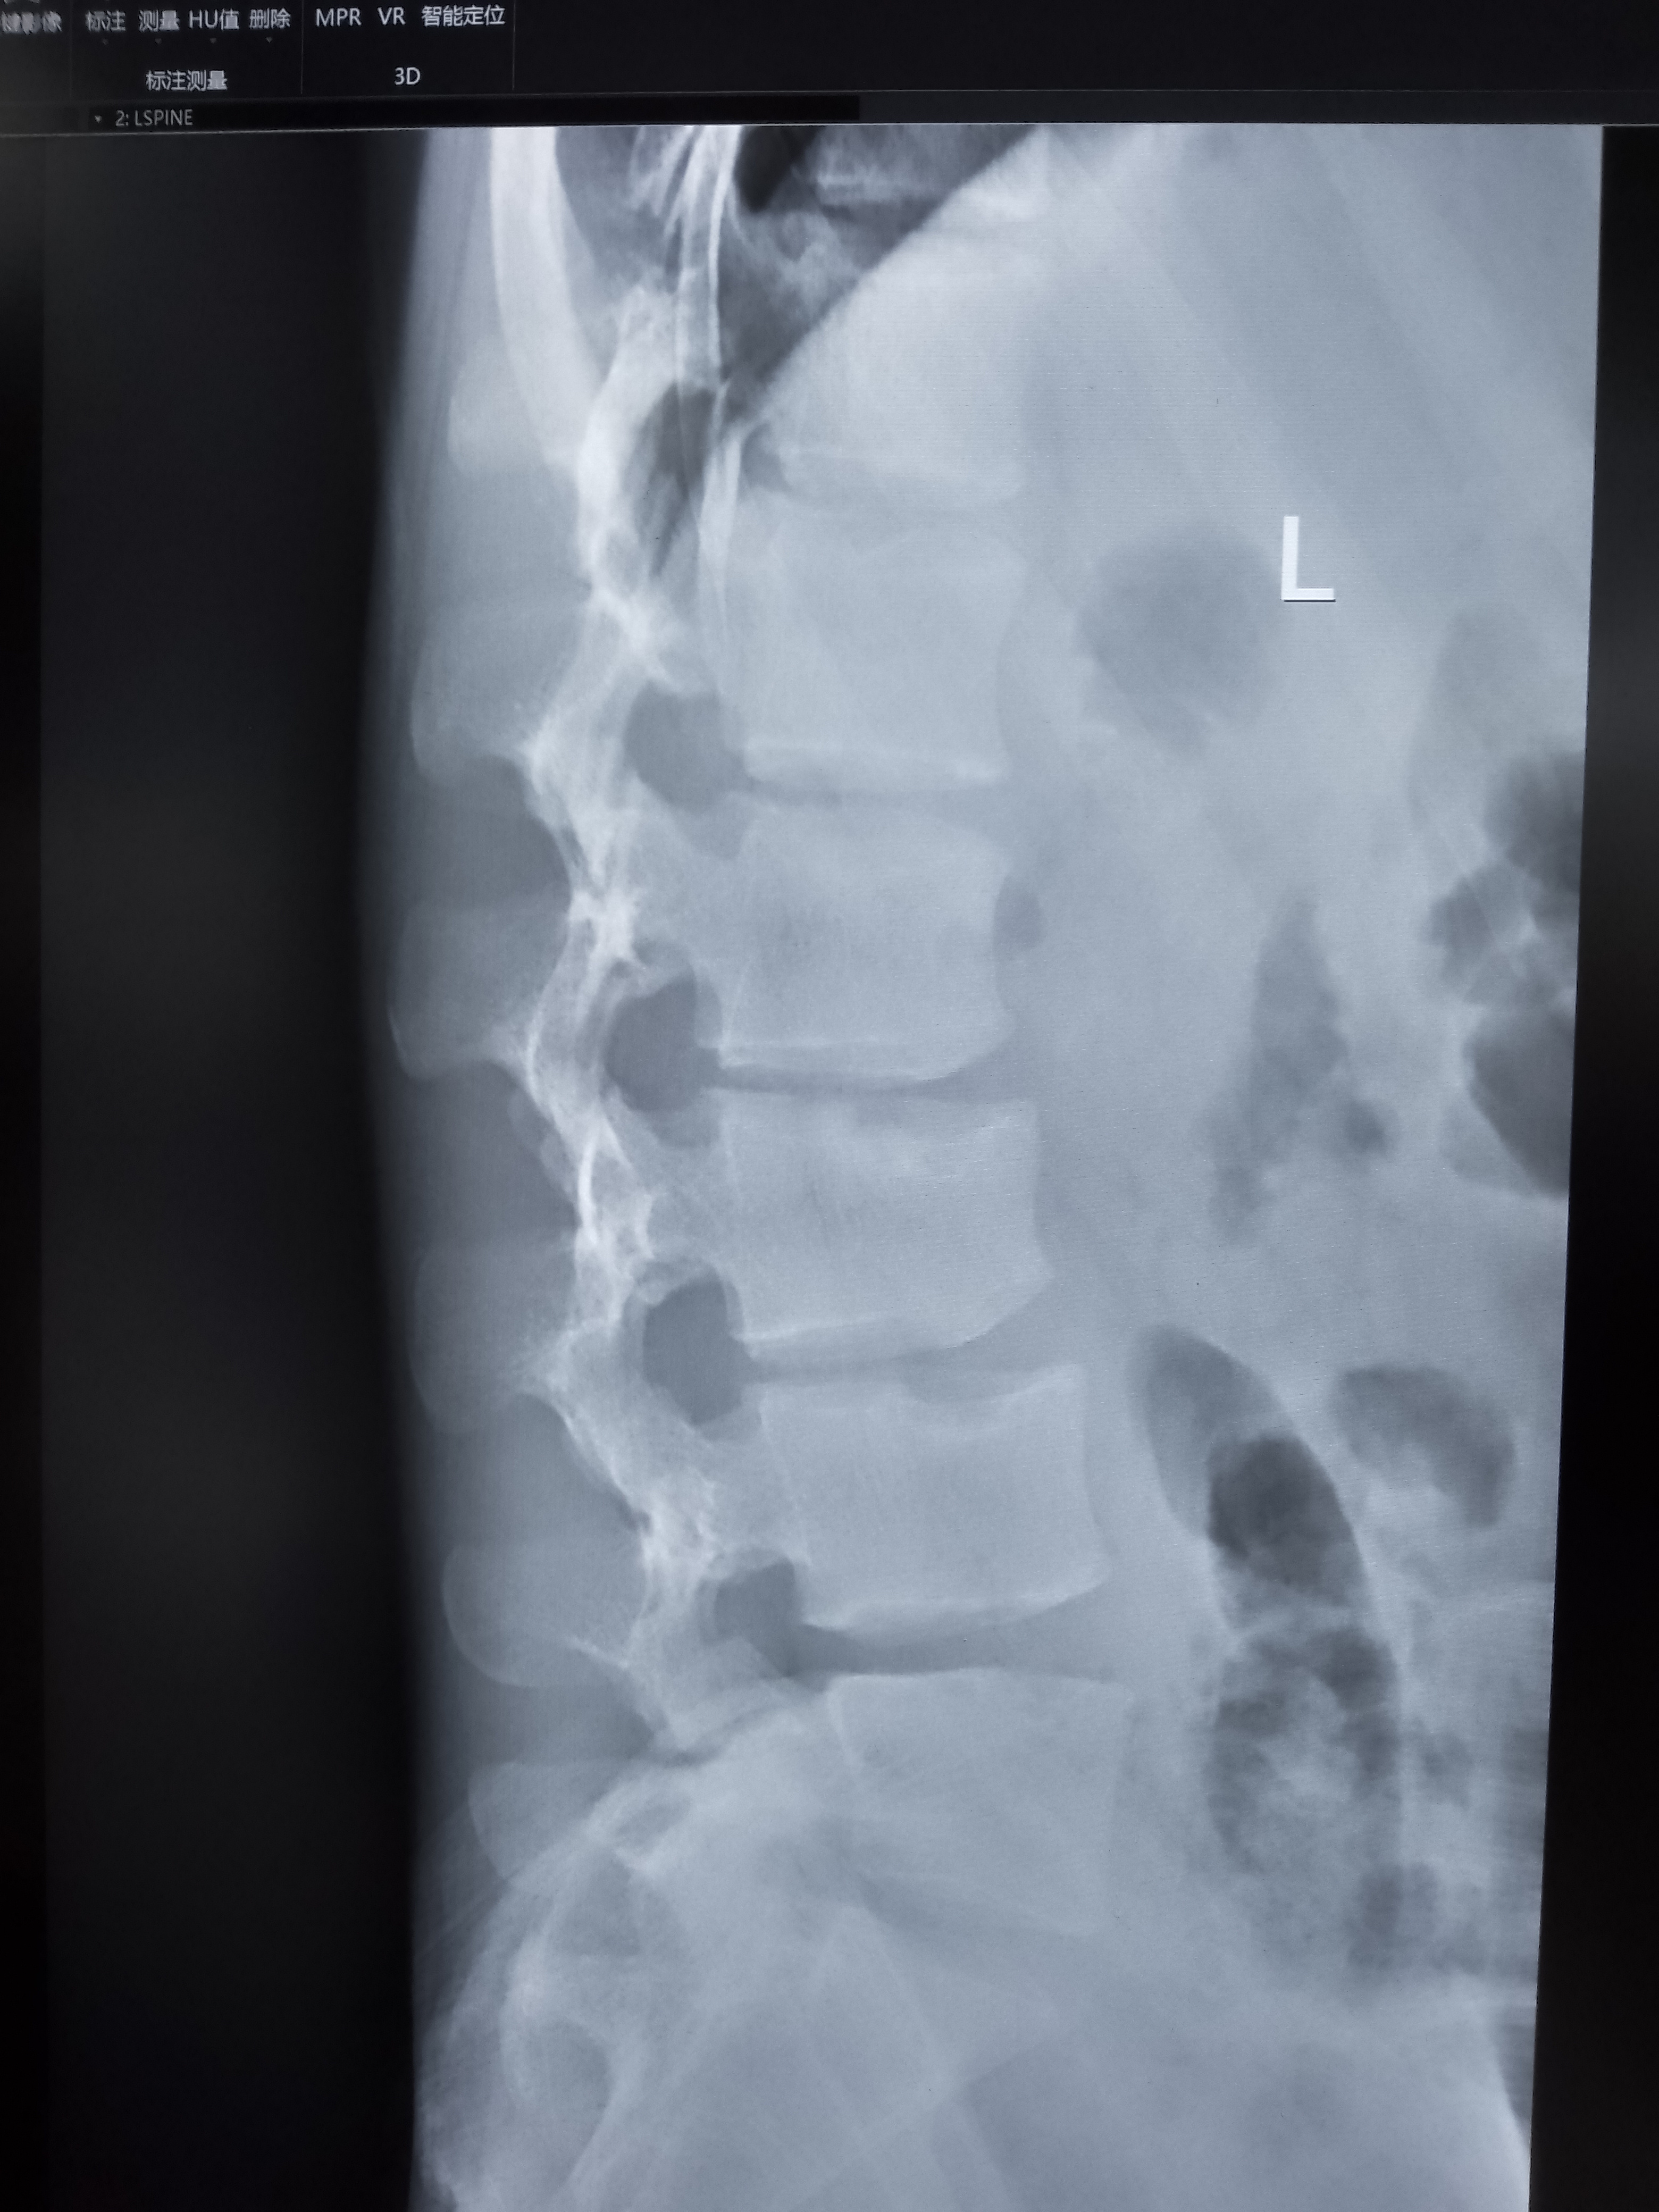

脊柱相关scheuermannsdisease休门氏病

图片尺寸1080x652